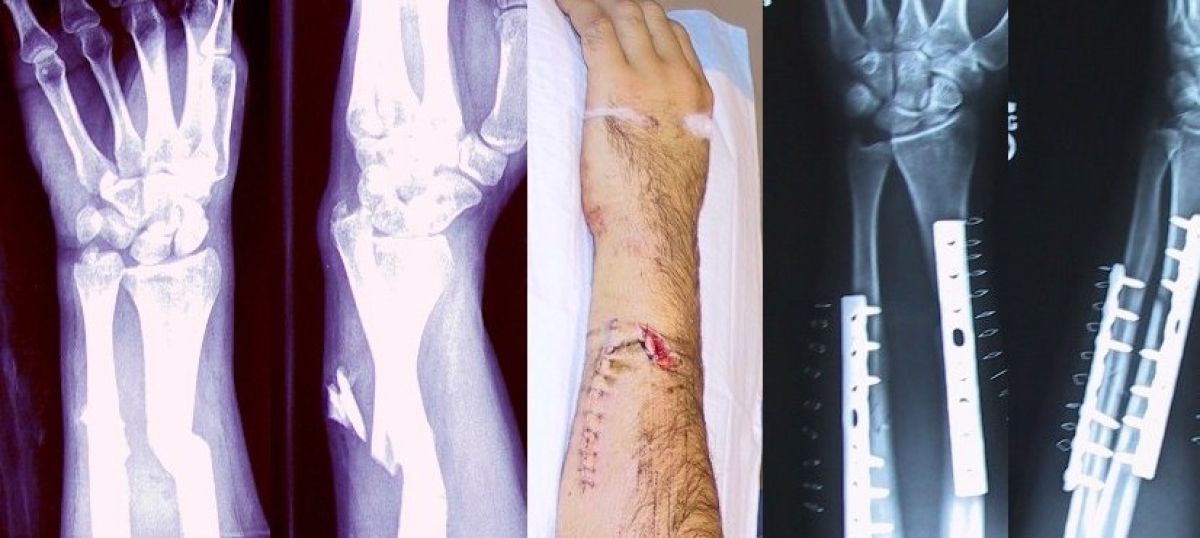

Cena letalskih kart za "pobeg" iz Rusije so poletele v nebo, na mejnih prehodih z Gruzijo, Kazahstanom in Mongolijo se vijejo dolge vrste avtomobilov. Ruski moški in njihove partnerke na spleti iščejo informacije o tem, kako si doma zlomiti roko, saj bi se s tem lahko izognili vpoklicu.

Broken_fixed_arm.jpg

wikipeda

V primeru samopoškodbe Rusom grozi kazenski pregon.

Da bi se izognili nesmiselni, krvavi vojni, prestrašeni moški in njihove partnerke in soproge preko iskalnika google iščejo nasvete, kako si doma zlomiti roko.

Ruske oblasti so se na poizvedovanja svojih državljanov odzvale s posebnim opozorilom, da potencialnim kandidatom za vpoklic grozi kazenski pregon, če se bodo samopoškodovali, da bi se izognili vpoklicu v vojsko.